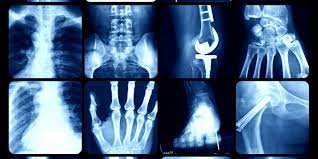

Staying active is one of the best things you can do for your health — but it also increases your risk of injury. Whether you’re a weekend warrior, a fitness enthusiast, or a competitive athlete, sports-related injuries can happen suddenly or develop gradually from overuse.

At New York Orthopedics, our orthopedic sports medicine specialists diagnose and treat all types of athletic injuries, helping patients recover quickly and return to the activities they love.

Knee injuries are among the most common sports-related conditions. The anterior cruciate ligament (ACL) helps stabilize the knee during cutting and pivoting motions — movements common in soccer, basketball, skiing, and football.

The rotator cuff is a group of four muscles and tendons that stabilize the shoulder joint. Injuries often result from overhead sports like tennis, baseball, and swimming.

Ankle sprains and Achilles tendon injuries are extremely common, especially in runners and court-sport athletes.

Lateral epicondylitis (tennis elbow) and medial epicondylitis (golfer’s elbow) are overuse injuries caused by repetitive arm and wrist motion. Despite their names, they affect athletes in many sports — as well as individuals who type or lift regularly.

The meniscus and joint cartilage are critical for shock absorption and smooth knee motion. These structures can be damaged by twisting injuries or degeneration over time.